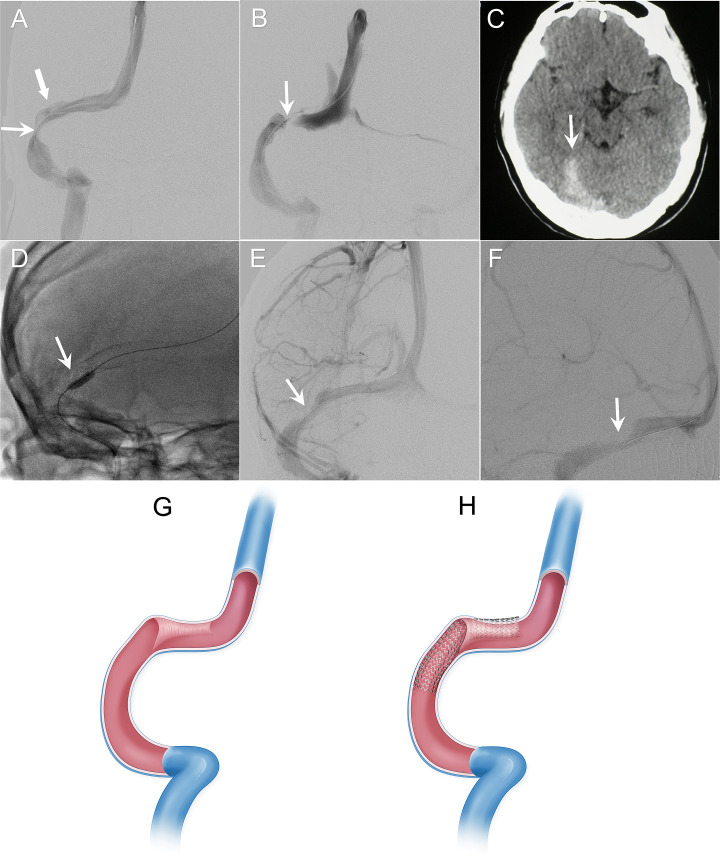

目的:硬膜窦中隔的存在在解剖学上早已被确认,但其临床意义却往往被忽视。我们的研究结果显示,硬脑膜窦中隔与静脉窦支架植入失败和并发症有关,并有临床证据支持:这项回顾性研究纳入了 2009 年 1 月至 2022 年 5 月期间接受脑静脉窦支架治疗的 185 例连续患者。我们使用数字减影血管造影术(DSA)确定了硬脑膜窦间隔,并根据其位置将其分为三种类型。位于横窦的隔膜被定义为 I 型,位于横窦和乙状窦交界处的隔膜被定义为 II 型,位于乙状窦的隔膜被定义为 III 型。根据解剖学特征和神经影像学线索,我们研究了硬膜窦间隔与支架植入失败和并发症的相关性:在 185 名患者(121 名特发性颅内高压患者和 64 名静脉性搏动性耳鸣患者)中,有 32 人(17.1%)通过 DSA 发现患有硬膜窦间隔。半数以上的隔膜为 I 型(18/32,56.2%),其次是 II 型(11/32,34.4%)和 III 型(3/32,9.4%)。硬膜窦隔膜导致了三例支架植入失败和并发症,包括一例静脉窦损伤伴硬膜下出血和两例支架扩张不完全。统计分析显示,硬膜窦间隔(pDiscussion:硬脑膜窦间隔是脑静脉窦的常见结构。我们发现硬膜窦间隔的存在给脑静脉窦支架植入术带来了不确定性,并提出了成像和治疗中的注意事项和巧妙技巧。

Results: 32 (17.1%) out of 185 patients (121 with idiopathic intracranial hypertension and 64 with venous pulsatile tinnitus) were identified with dural sinus septa by DSA. More than half of the septa were type I (18/32, 56.2%), followed by type II (11/32, 34.4%) and type III (3/32, 9.4%). The dural sinus septa caused three stenting failures and complications, including one case of venous sinus injury with subdural haemorrhage and two cases of incomplete stent expansion. Statistical analysis revealed that the presence of dural sinus septum (p<0.01) was associated with complications of cerebral venous sinus stenting.

Discussion: The dural sinus septum is a common structure in the cerebral venous sinus. We found that the presence of dural sinus septa introduces uncertainties to cerebral venous sinus stenting and suggested precautions and ingenious skills in imaging and treatment.